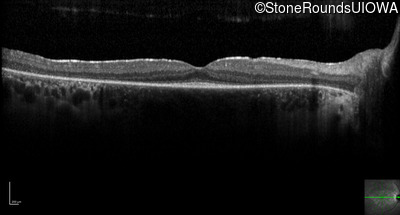

Optical Coherence Tomography - Right -

20/20 -1

Exemplar / OCT Stack